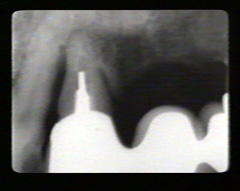

Las radiografías periapicales muestran pérdida de hueso alveolar en aproximadamente la mitad de la longitud de la raíz. La pérdida de hueso en el área de furacación se indica por la radiolucidez aumentada en la unión de las raíces en la región cervical.

Los premolars han perdido más de la la mitad de la longitud de la raíz del hueso alveolar periodontal.  Hay defectos infraóseos en particular en el segumdo premolar en mesial y distal. El modelo semilunar que cubre la raíz del segundo premolar también indica la presencia de una defecto óseo en palatino.

En mesial del lateral derecho como en distal del central derecho aparece una perdida considerable de hueso. El puente fué realizado hace unos seis años como consecuencia de un accidente automovilístico.